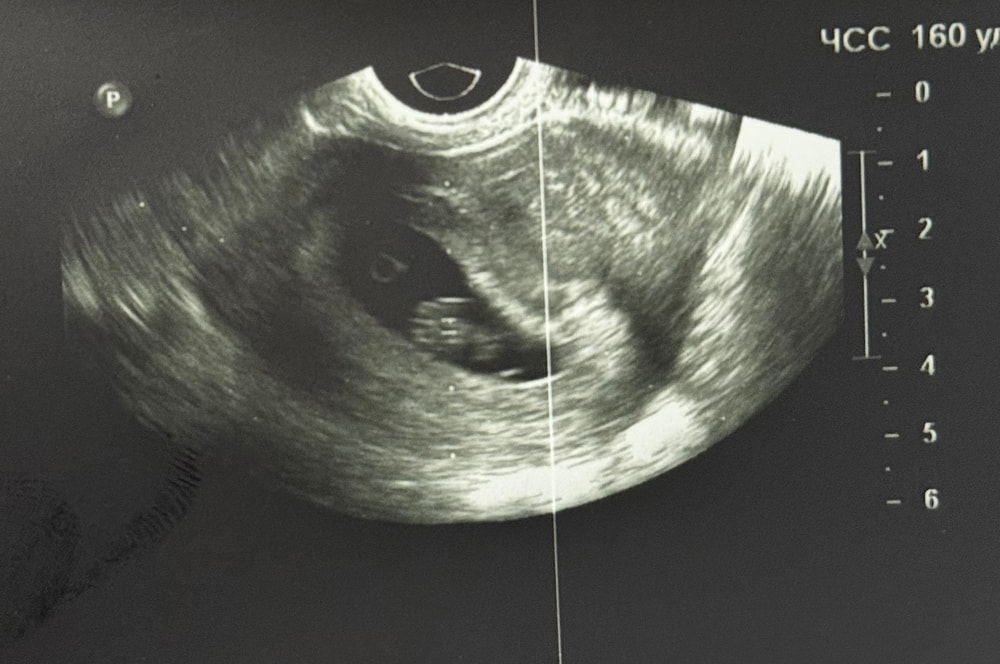

УЗИ, КТГ, доплерДевочки, может кто сталкивался. Сходила на узи. Срок 7,5нед. КТР 14, СБ 160. Узист ничего плохого не сказала, кроме тонуса. Еду домой, читаю заключение. Желточный мешочек 6,7 мм. Естественно в интернете ничего хорошего это не значит. Написала доктору. Она сказала главное сб есть и ктр растет. На душе все равно тяжко. Но логически, это значит жм почти половина эмбриона. А на узи жм не большой😭